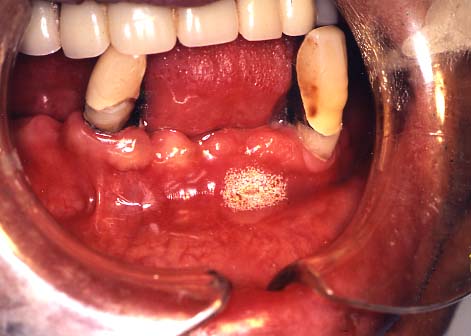

(3)口内炎

1.白く口内炎が出来ています。

さわると痛く,食べるとしみます。